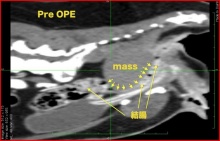

CTの結果・・・ラブちゃんの骨盤の中には大きなしこりがあって、それが腸を圧迫してウンチの通りが悪くなっていることが確認されました。

写真がCT検査の画像で、「mass」と書いてあるのがラブちゃんの骨盤腔内にできたしこりで、結腸を矢印のように圧迫しているのがよくわかると思います。